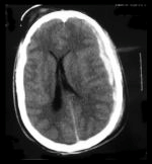

Quel diagnostic sur ce scanner?

Hématome sous-dural gauche avec effet de masse déviation de la ligne médiane